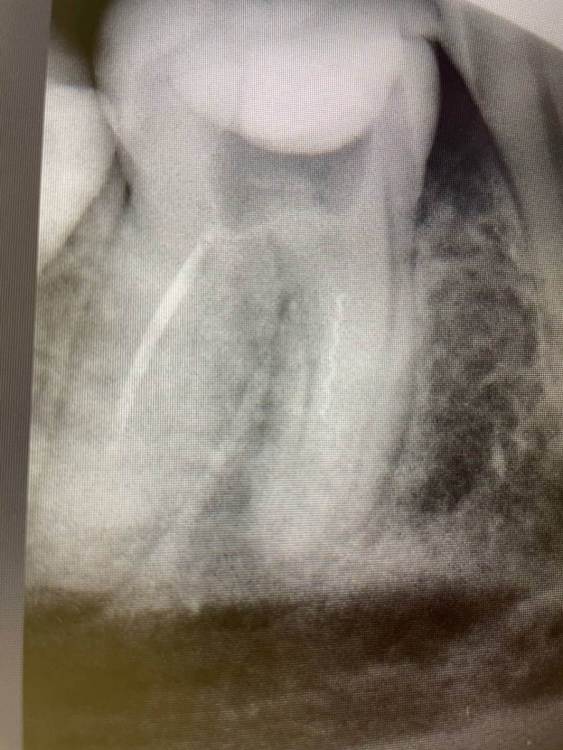

1586Doc Опубликовано 8 декабря, 2021 Автор Поделиться Опубликовано 8 декабря, 2021 Добавим эндо) Ретрит 46 зуб, 2 фрактуры в медиальных каналах. Один достаем, второй обходим )) 1 3 Ссылка на комментарий